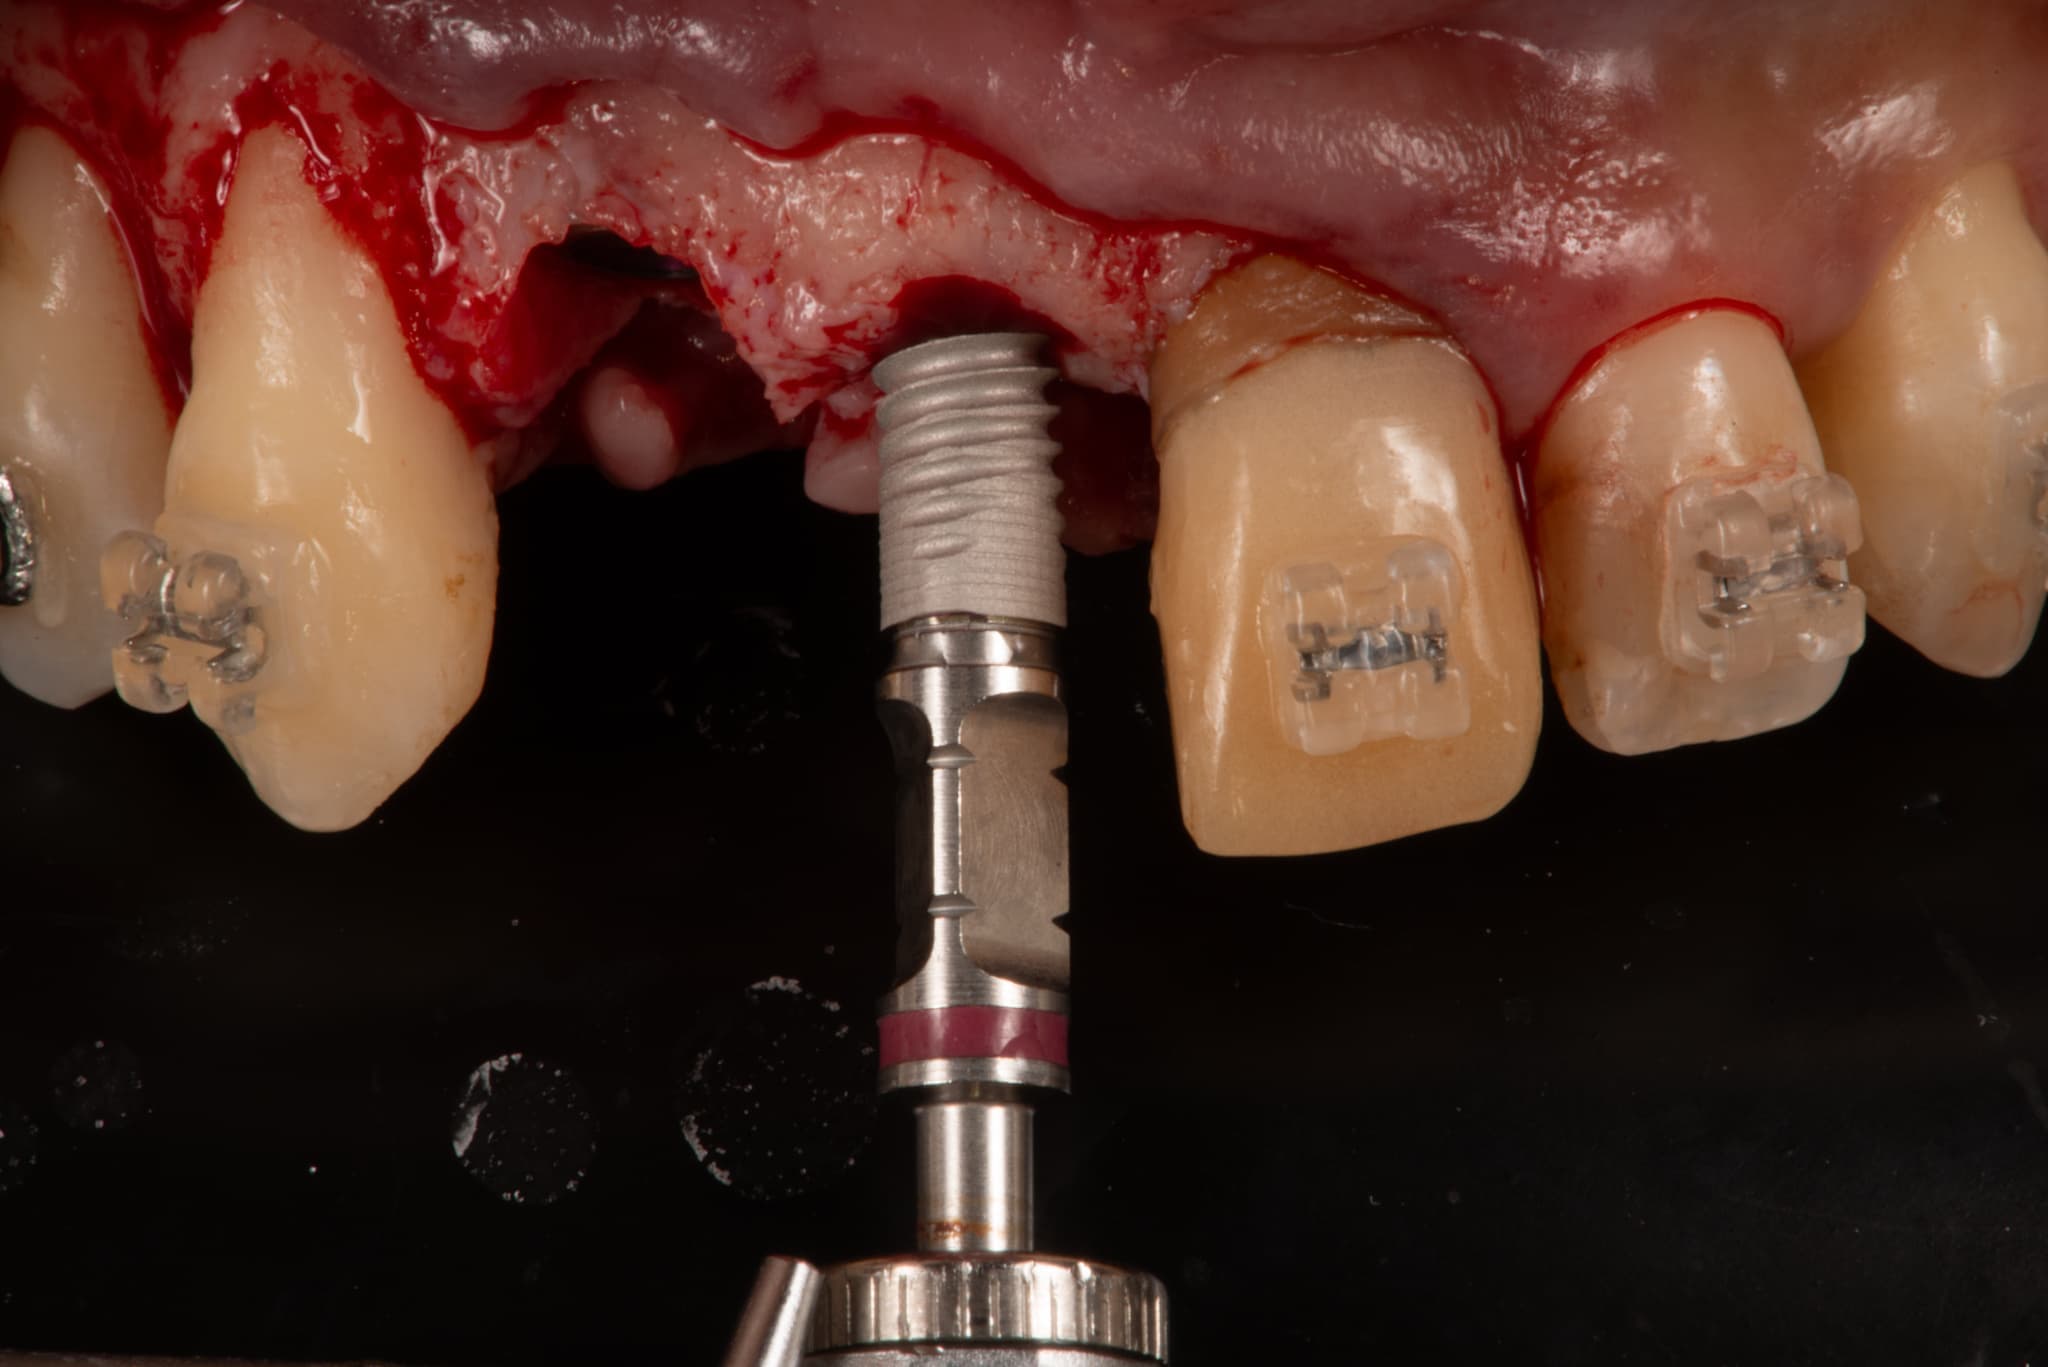

CT診断、CAD/CAMを活用した最先端の治療を行います

インプラント治療は失ってしまった歯の替わりに、 生体親和性が極めて高い純チタンで出来たインプラント(人工歯根)を歯肉内部にある顎の骨に埋め込み、その上に人工の歯を取り付け、噛み合わせを回復する治療法です。

CT設備完備

二次元のレントゲン(歯科医院にある通常のレントゲン)では見えなかったこと、分からなかったことが、歯科用CTなら正確な診査と診断ができ、安全性と治療のクオリティーを高めることが可能となります。

インプラント手術においてCT撮影は必須です。CT撮影を行うか否かも医院を選ぶうえでの判断材料にしていただければと思います。

ンピューター診断

手術時の「人為的なミス」を最小限に抑えることができる安全なインプラント治療を望まれる方。ぜひ、コンピューターインプラントを実施している医院での受診を強くお勧めします。

科手術

術前の診断を手術に生かします。

シュミレーションした場所に確実にインプラントを設置していきます。